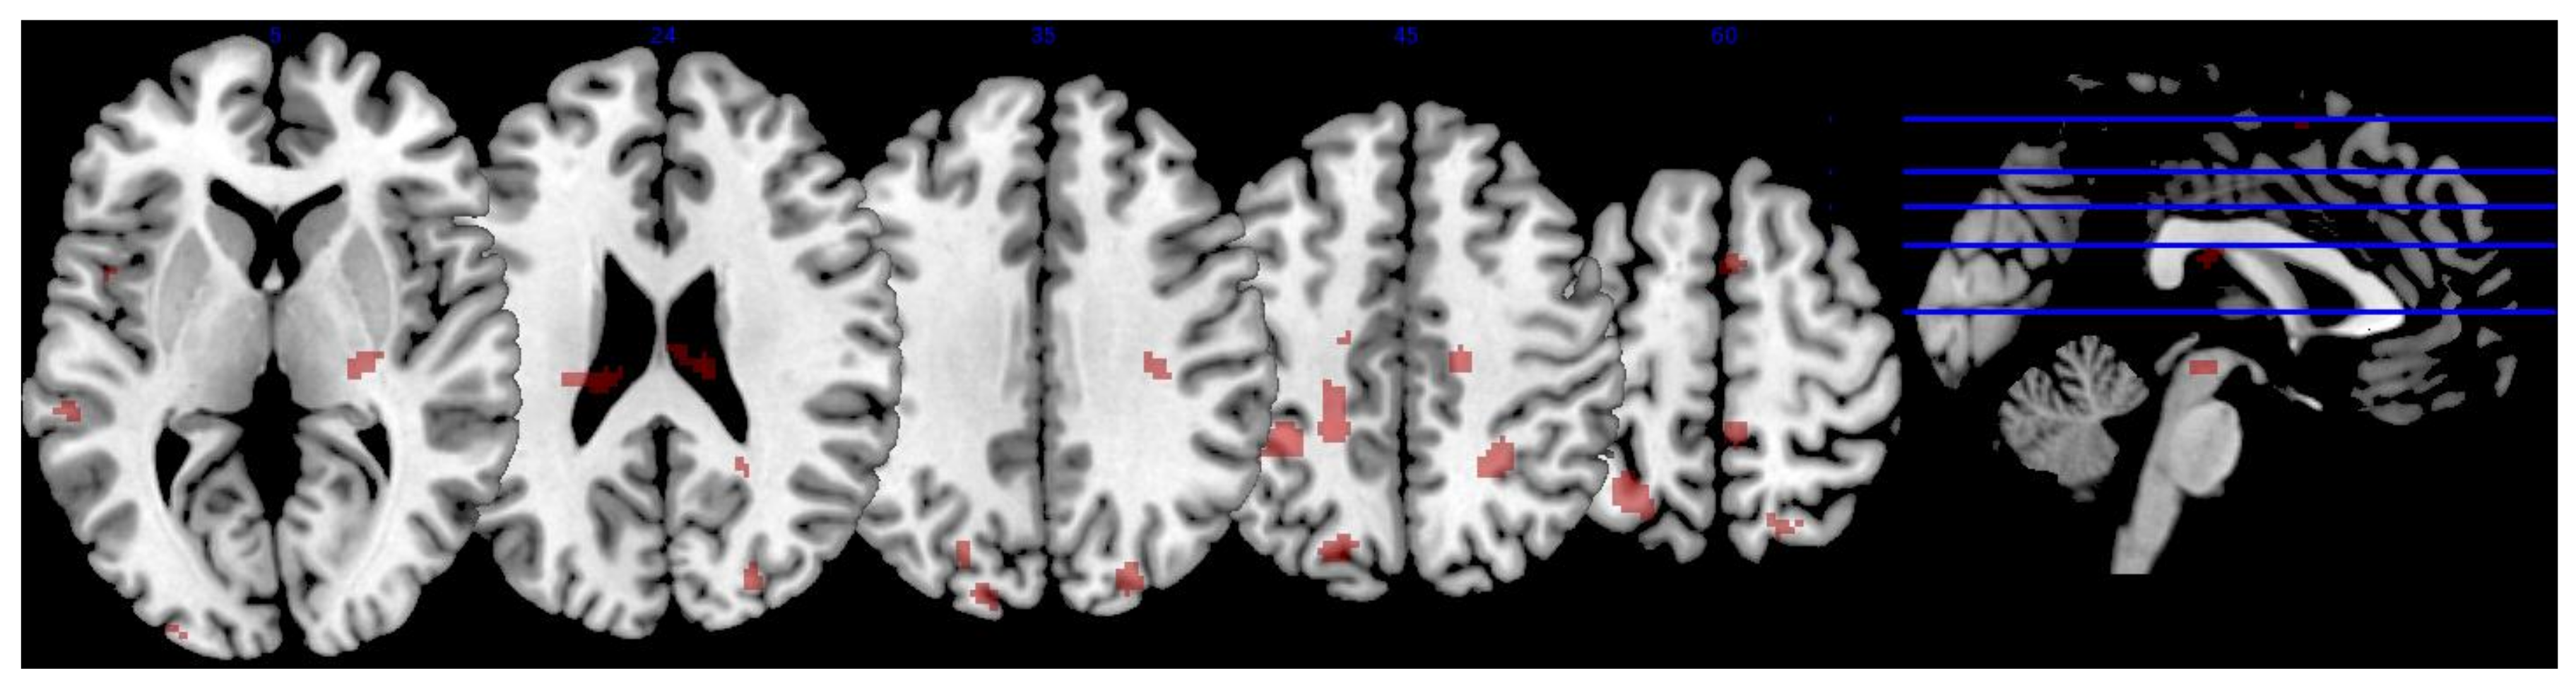

3.3.1. MPOD

| Region | x | y | z | Extent | T-Score | Effect Size (r) |

|---|---|---|---|---|---|---|

| R precentral gyrus | 16 | −18 | 48 | 62 | 3.75 | 0.492 |

| L middle temporal gyrus | −56 | −8 | −12 | 51 | 3.55 | 0.472 |

| L superior parietal lobule | −36 | −42 | 50 | 199 | 3.46 | 0.462 |

| −28 | −56 | 58 | * | 3.29 | 0.444 | |

| L superior lateral occipital cortex | −20 | −74 | 40 | 61 | 3.42 | 0.458 |

| −16 | −88 | 36 | 12 | 2.73 | 0.381 | |

| R temporal fusiform cortex | 36 | −30 | −16 | 33 | 3.36 | 0.452 |

| L precentral gyrus | −20 | −40 | 44 | 68 | 3.32 | 0.448 |

| R superior lateral occipital cortex | 26 | −84 | 30 | 67 | 3.21 | 0.436 |

| 24 | −62 | 56 | 51 | 3.04 | 0.417 | |

| L superior frontal gyrus | −22 | 30 | 54 | 28 | 3.16 | 0.430 |

| L posterior superior temporal gyrus | −60 | −32 | 4 | 49 | 2.92 | 0.403 |

| L planum temporale | −62 | −22 | 6 | * | 2.70 | 0.377 |

| L superior temporal gyrus | −52 | −38 | 2 | * | 2.56 | 0.360 |

| L occipital pole | −28 | −96 | 6 | 9 | 2.99 | 0.411 |

| L temporal fusiform cortex | 44 | −16 | −16 | 9 | 2.95 | 0.406 |

| R thalamus | 24 | −22 | 4 | 36 | 2.93 | 0.404 |

| L planum polare | −36 | −8 | −10 | 19 | 2.87 | 0.397 |

| R posterior supramarginal gyrus | 46 | −38 | 10 | 21 | 2.58 | 0.362 |

| R posterior superior temporal gyrus | 54 | −36 | 8 | * | 2.87 | 0.397 |

| L Heschl’s gyrus | −46 | −22 | 2 | 12 | 2.83 | 0.392 |

| L parahippocampal gyrus | −32 | −36 | −18 | 22 | 2.83 | 0.392 |

| R postcentral gyrus | 6 | −40 | 62 | 22 | 2.66 | 0.372 |

| L central opercular cortex | −48 | 6 | 2 | 11 | 2.75 | 0.383 |

| R anterior middle temporal gyrus | 58 | −2 | −22 | 19 | 2.70 | 0.377 |

| R anterior superior temporal gyrus | 50 | −2 | −16 | * | 2.62 | 0.367 |

| L temporal pole | −52 | 6 | −18 | 10 | 2.67 | 0.373 |

| R lingual gyrus | 18 | −60 | −16 | 8 | 2.61 | 0.366 |